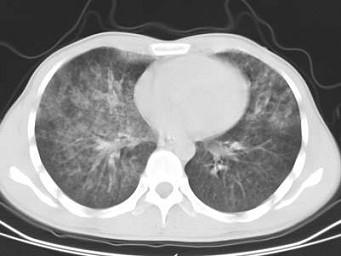

问题 男,32岁,咯血,咳痰一周,胸部CT如图,最可能的诊断为 ( )

选项 A、右上肺结核性空洞并霉菌感染 B、组织胞浆菌病 C、周围型肺癌 D、右上肺感染 E、肺结核

答案 A